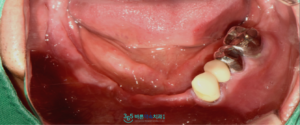

먼저 구강 내를 확인한 결과,

위아래 모두 부분 틀니를 사용 중이셨습니다.

특히 불편감을 호소하셨던 아래턱의 잔존 치아는

심한 잇몸 질환과 지속적인 과도한 힘의 영향으로

전반적으로 약해져 있었으며,

동요도가 큰 상태로 확인되었습니다.